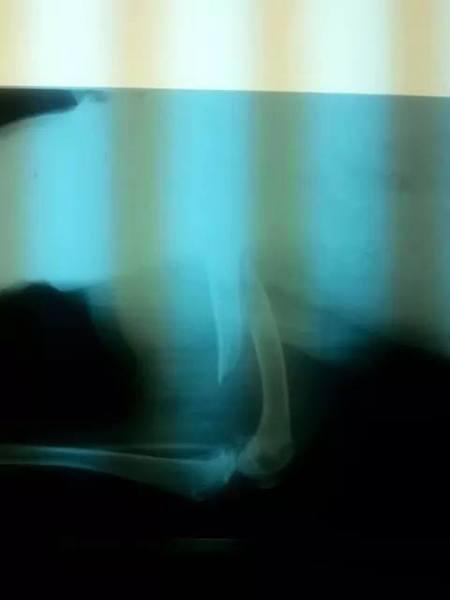

Die neuen Röntgenbilder haben ergeben, dass Jonas Becken, seine Hüfte und sein Knie gebrochen sind.

Jona wurde vor mehr als 6 Wochen bei einem Autounfall schwer verletzt.

Jona wurde in eine Tierklinik gebracht und Röntgenbilder wurden in Auftrag gegeben.

Dear friends Coyle was at vet clinic we did blood tests and x -ray. X - ray showed our dear boy has ileus, condition was so bad he did not had stool for more weeks so vets rushed him to surgery.

Er hatte einen Autounfall bei dem er schwer verletzt wurde.

Beim Tierarzt wurde festgestellt, dass der Gelenkkopf seines

Oberschenkels aus der Gelenkpfanne gerutscht war und schwer

beschädigt wurde.

Es wurde eine Femurkopfresektion vorgenommen, doch leider

wurde

bei der Operation ein Spiralbruch des Oberschenkelknochens übersehen.

2 Wochen nach der OP brach sein komplettes Bein.

Bruce wurde ein Nagel eingesetzt, der mit Drähten fixiert wurde.

Heute, gute 4 Wochen nach dieser OP dann der Schock - Sein

komplettes Bein ist infiziert, die Drähte, die den Nagel halten sollten

sind gebrochen und bereits in die Knochenhaut eingewachsen. Bruce

hat furchtbare Schmerzen.